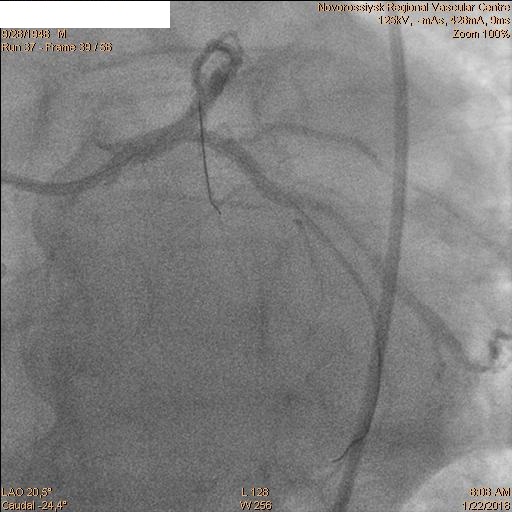

В 06.00 пациент в экстренном порядке подан в рентгеноперационную. Пациенту выполнена коронарография, по данным которой выявлены стеноз ствола ЛКА 60% с переходом на устья ПНА и ОА, окклюзия ПНА от устья и стеноз устья ОА 60%.

После которой было принято решение о выполнении бифуркационного стентирования ствола ЛКА.

Последовательно заведены коронарные проводники в дистальные сегменты ПНА и ОА. Первым этапом была выполнена реканализация, баллонная ангиопластика ПНА баллоном 2.5х20 мм и стентирование ствола ЛКА с переходом на проксимальный сегмент ПНА стентом 4.0х28 мм.